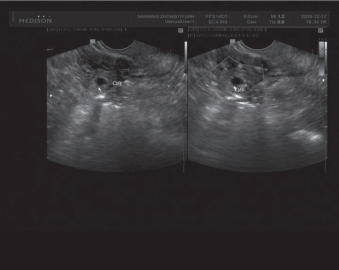

异位妊娠超声检查特征[2]:①急诊型.急诊型异位妊娠患者超声检查结果为子宫增大,但增大幅度较小,部分患者子宫内膜可出现增厚现象,其盆腔与腹腔内均出现较大暗性区域,患者子宫附件于上述暗性区域中处于漂浮状态,部分患者可见不规则包快回声;②相对稳定型.相对稳定型异位妊娠患者超声检查结果为子宫增大,但增大幅度较小,部分患者子宫内膜可出现增厚现象,其宫腔内未出现典型的双环状妊娠囊,宫腔外明显可见异常包快,部分患者盆腔内部可出现积液.

腹部超声检查能够清晰显示患者腹腔积液情况,并对暗性区域进行声窗,扫查范围广,可对腹腔情况进行全面显示,是临床常用的异位妊娠诊断方式.但临床研究表明,腹部超声检查结果易受到外界因素影响,如患者腹部脂肪、膀胱是否充盈、肠气以及瘢痕组织等,因此检查结果与病理证实准确率较低,尤其是体内出现直径较大或位置较高的包快时更易发生漏诊现象.但在急性异位妊娠患者中,由于患者腹部出现大出血情况,因此不需进行膀胱充盈,直接利用腹部暗性区域进行声窗,节省检查准备时间,给予正确诊断后进行治疗,为患者赢得抢救时间,保障患者生命安全[3].

阴道超声检查由于仪器探头更为接近靶器官,因此能够对患者宫腔、附件、子宫内膜进行准确显示,正确进行真假妊娠辨别,且受外界因素(如膀胱充盈、腹部脂肪、腹部瘢痕等)影响较小,因此检查结果更为准确.但急性异位妊娠患者不易选用此种超声检查方式,其原因为患者腹腔内大量出血,探头进入无法准确检查,且可能会对患者腹腔造成伤害,加重患者病情,造成严重后果[4].